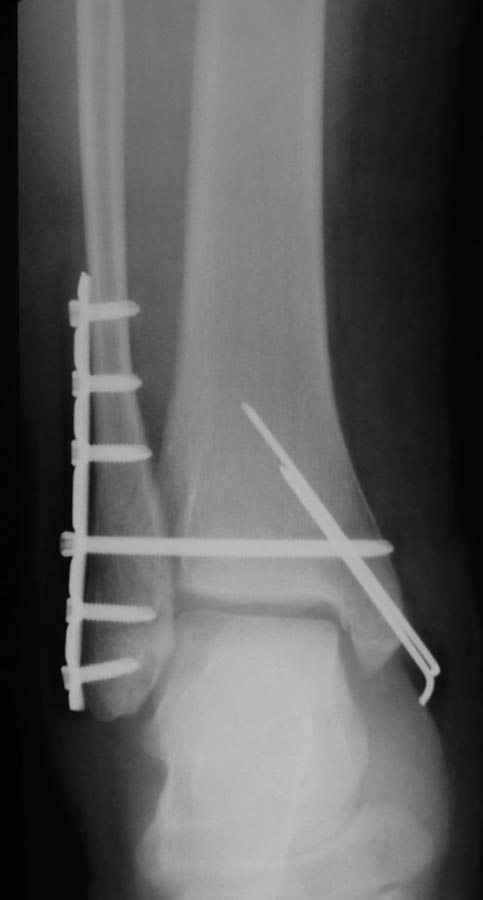

Девушка 30 лет была прооперирована через несколько часов после травмы

(до- и послеоперационные снимки представлены). До операции обращали на

себя внимание выраженный дефицит тыльного сгибания другой стопы и

обширные натоптыши под головками центральных плюсневых костей на обеих

стопах. При сгибании коленного сустава сгибание со значительным

усилием в голеностопном суставе на здоровой стопе едва достигало 90 гр.

Такой же объем движений был выявлен и на операционном столе на

травмированной ноге после выполненияостеосинтеза. Раньше, несмотря на

наличие натоптышей, стопы не болели. К выписке, на четвертые сутки,

пациентка могла ходить с опорой на всю стопу в обуви с приподнятой на 4

см пяткой.